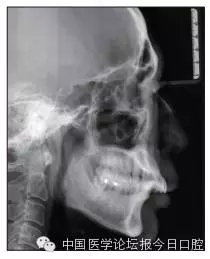

X線檢查

全口曲面體層片(圖3)顯示,患者全牙列牙槽骨吸收;根尖片(圖4)示11近中牙槽骨角形吸收已達(dá)根尖1/3,21牙槽骨嵴頂吸收至根1/2,23牙槽骨近中骨板角形吸收至根1/2。磨牙區(qū)骨嵴頂吸收3mm。治療前頭顱側(cè)位片見(jiàn)圖3,治療前ODS模型見(jiàn)圖5。

圖3 治療前頭顱側(cè)位片及曲面體層片